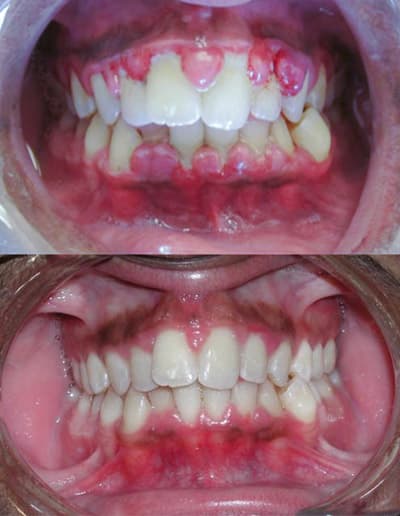

La gingivite est une inflammation de la gencive, associée ou non à des phénomènes dégénératifs, nécrotiques ou prolifératifs et causée par la plaque bactérienne. La gingivite est une maladie parodontale, c'est-à-dire une maladie touchant le parodonte, les tissus entourant la dent. Une gencive saine présente un aspect « en peau d'orange », rose pâle, et ne saigne pas au contact. Lors de la gingivite, la gencive devient rouge (toute variation de couleur signe une situation pathologique), lisse et gonflée. Elle saigne facilement, soit lors du brossage, soit parfois même spontanément. On peut observer des poches parodontales, c'est-à-dire un espace qui se forme entre le haut de la gencive et le niveau où elle s'attache à l'os. La gingivite peut être localisée ou généralisée, marginale, papillaire, diffuse. C'est la gingivite habituelle, inflammation de la gencive due à la plaque dentaire. Ses signes sont : rougeur ; œdème (papilles boursouflées) ; gencive brillante, vernissée (la piqueté disparaît) ; saignements fréquents. Il peut y avoir formation de poches parodontales. Elle n'est pas douloureuse. On observe une augmentation de volume importante (parfois on ne voit même plus les dents). La gencive est très fibreuse ; la texture et la teinte restent normales (car on ne voit pas la partie enflammée). L'étiologie est la prolifération des fibroblastes. Elle est parfois d'origine idiopathique, mais le plus souvent elle est favorisée par certains médicaments : certains anti-épileptiques, la ciclosporine, la nifédipine et certains bêta-bloquants). Il s'agit d'une tumeur framboisée. La teinte est prononcée, la texture vernissée ; la profondeur du sillon augmente beaucoup (jusqu'à 7- au lieu des 2 à 3 habituels) ; saigne très facilement. Aussi appelée gingivite gravidique, elle est favorisée notamment par certaines hormones féminines (fréquent chez la femme enceinte). Dans ce cas très particulier, on a affaire à une destruction tissulaire par nécrose, sans formation de poche.